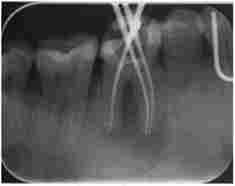

перше відвідування пацієнта включає підготовчий етап. Препарують зуб, розробляють гирла кореневих каналів, створюють прямолінійний доступ в канали. Поетапно евакуюють розпад пульпи з каналів. Виконують ендодонтичне лікування. Промивають канали, здійснюють іригацію кореневого каналу розчинами на основі ЕДТА, гіпохлориту натрію, ферментами з антибіотиками, його розширюють, формують з використанням ендодонтичного інструменту (рис. 6.2). В результаті видаляється біоплівка зі стінок кореневого каналу, змащений шар. Канал промивають, сушать і тимчасово пломбують препаратами з гідроксидом кальцію, зуб герметично закривають на 7-14 діб.

Візіограмма зуба 4.6. Контроль проходження кореневих каналів з ендоінструментамі

Мал. 6.2. Візіограмма зуба 4.6. Контроль проходження кореневих каналів з ендоінструментамі